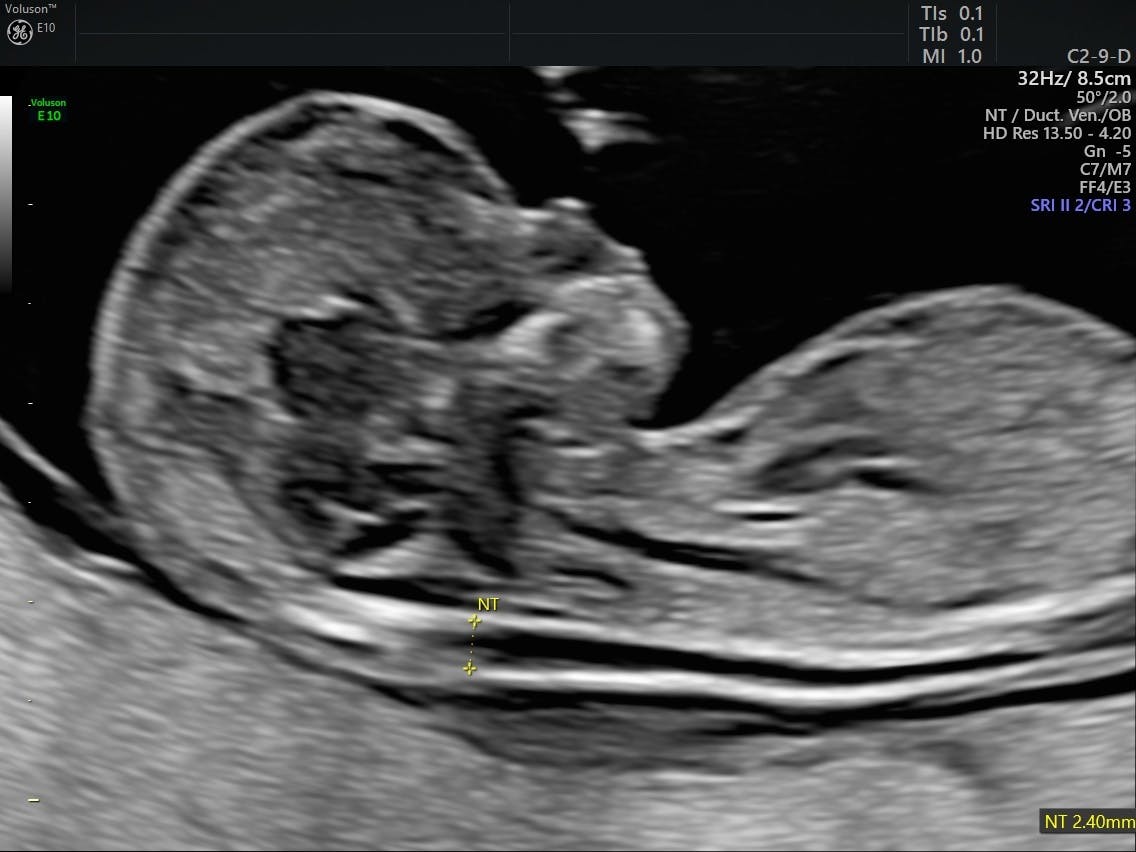

The sonographer first confirms your baby's gestational age by measuring him from crown to rump to see whether he's about the size he should be for his age. A nuchal scan measures the translucent space in the nuchal fold at the back of your baby's neck. The nuchal scan is a relatively new development but is now routinely carried out in most countries. Anterior low means low lying placenta.placenta can be anterior or posterior or fundal.these are the different positions of placenta in the uterus.low means low i usually have severe lower abdominal pain on the first day of the periods, does this anyway affects my womb or placenta or its placement? Nuchal translucency scan is part of the ultrasound scan that most pregnant women have at around 12 week of pregnancy. The nuchal translucency scan or nt scan measures the clear (translucent) space in the tissue at the back of your child's neck. The nuchal translucency scan looks at an area called the nuchal fold, which is visible during the ultrasound at the back of your baby's neck. The nuchal scan is used in pregnancy to determine if the baby is likely to have a condition such as down's syndrome.

The nt scan measures the amount of fluid behind the fetus' neck. Ns abbreviation stands for nuchal scan. As the nt increases, so does the chance of down's syndrome and other chromosomal abnormalities. In this momjunction post, we tell you when this procedure is done, why it is done, and during this time, the fetal lymphatic system is at its developing stage, and the placenta's peripheral resistance is high, which means it is the right time to. A nuchal scan indicates the likelihood of some genetic abnormalities, including down's syndrome. Nuchal translucency scan is part of the ultrasound scan that most pregnant women have at around 12 week of pregnancy. A nuchal scan measures the translucent space in the nuchal fold at the back of your baby's neck. A nuchal translucency test, or nt test, is a noninvasive ultrasound that can screen for chromosomal disorders such as down syndrome.

This is done by scanning the thickened nuchal fold do exist with babies with downs. A nuchal scan or nuchal translucency (nt) scan/procedure is a sonographic prenatal screening scan (ultrasound) to detect cardiovascular abnormalities. What do my nt scan results mean? A nuchal translucency scan, also known as an nt scan, is a prenatal screening test done by ultrasound that helps to calculate the baby's risk of being born with down syndrome and certain other chromosomal disorders. When the nt is greater than 3.5 mm, there is a 1 in 5 chance of a chromosome abnormality such as turner or down what does this mean? Neck scan is a basic ct method for clarifying neck lesions. The nuchal scan (nt scan) is a screening done during an antenatal ultrasound to measure the amount of fluid at the base of your baby's neck. All babies have a certain amount of fluid in this area. What is the meaning of nuchal scan in various languages. The fluid in this nuchal fold can be measured to determine if it is within the normal range. You'll receive a letter telling you when to come in. A nuchal scan indicates the likelihood of some genetic abnormalities, including down's syndrome. The nuchal scan is a relatively new development but is now routinely carried out in most countries.